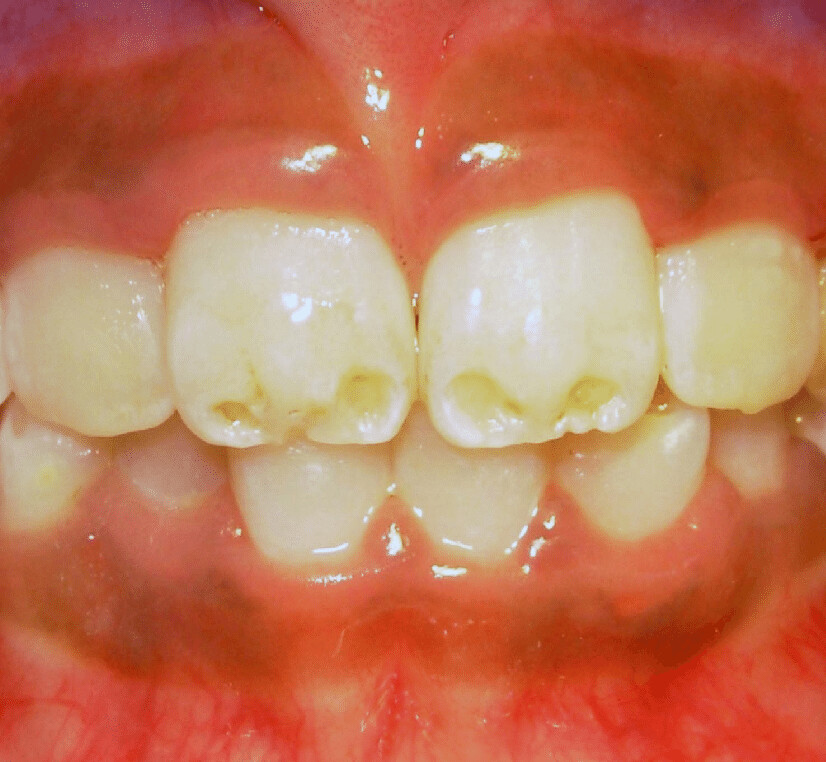

Enamel hypomineralisation happens when the mineralisation process is not fully achieved, resulting in discoloured enamel. This condition also weakens the teeth, which means that teeth can break down. The Australian Academy of Pediatric Dentistry also explains that hypomineralisation is prevalent in a fifth of all children. It can appear as discoloured patches of soft or decaying, bumpy enamel that usually affect the molars and incisors as they grow in. Teeth with hypomineralisation are sensitive and can cause children pain when eating; these teeth typically start to deteriorate once they grow in.

There are several causes as to how and why these conditions form. According to the Indian Journal of Dentistry, these conditions occur when there is a disturbance in the matrix formation of the teeth. To break that down, let’s look at ameloblasts, which are your teeth’s enamel-producing cells. These cells form in six stages: morphogenetic, organising, formative, maturative, protective, and desmolytic. Enamel hypoplasia happens in the formation stage, resulting in the pitting, grooving, or even total absence of enamel. Hypomineralisation happens in the maturative stage and can appear as “chalky” areas on your tooth’s enamel.